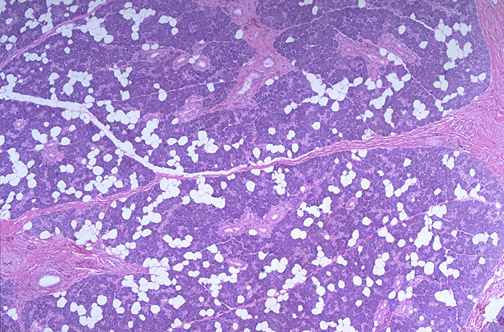

| Normal parotid salivary gland is seen here at low power. Parotid is composed of serous cells that contain dark granules from which enzymes such as amylase and maltase are released. There are admixed fat cells, and between lobules of acini are connective tissue septae through with the larger ducts are found. |